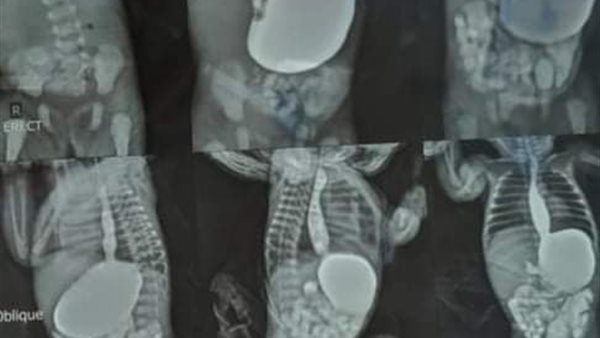

تم إجراء عملية جراحية لطفلة عمرها 16 يومًا بوزن 1.600 كيلو جرامًا تعاني من اللتواء خلقي بالأمعاء، وتم إصلاح الالتواء واستئصال الزائدة الدودية والطفلة الآن بحالة جيدة.

كما حضرت طفلة بعد أربع ساعات من ولادتها بوزن 2 كجم تعاني من فتق خلقي بجدار البطن، وتم على الفور التدخل الجراحي وإرجاع الأمعاء داخل البطن وإصلاح الفتق والطفلة بحالة جيدة.

في هذا السياق، حضر طفل عمره 8 أيام وزنه 2.500 كجم يعانى من وجوده كيس خلقي بالأمعاء أدى إلى انسداد والتواء بالأمعاء وحدوث ثقب بالأمعاء، وتم التدخل الجراحي واستئصال الكيس وإعادة توصيل الأمعاء والطفل بحالة جيدة.